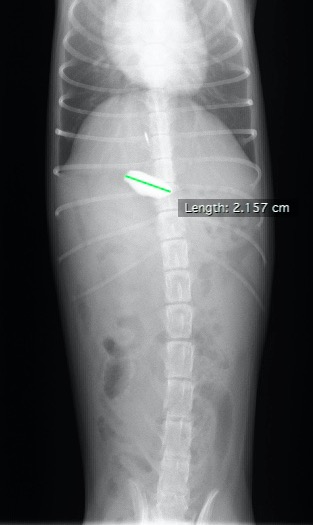

仰向けでのX線写真。